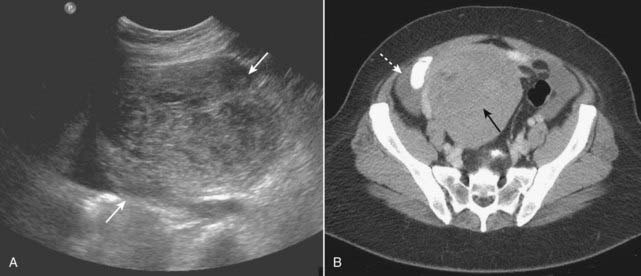

Medical Renal Disease

image Medical renal disease refers to a host of diseases that primarily affect the renal parenchyma. They include such diseases as glomerulonephritis, diseases that cause nephrotic syndrome, and renal involvement in collagen vascular diseases.

image In the early stages of medical renal disease, the kidneys may appear normal. Later, changes in the echo architecture occur but these are usually nonspecific as to the actual etiology. The renal parenchyma becomes more echogenic (brighter) than the liver and spleen, the reverse of the normal echo pattern. Renal size is also an important reflection of the chronicity of a disease, the renal parenchyma almost always decreasing in size with chronic disease. A biopsy may be performed to determine the etiology of the disease (Fig. 19-11).

image

Figure 19-11 Chronic medical renal disease, sagittal view.

The right kidney (K) is small, measuring 6 × 3 cm between cursor marks. The renal parenchyma (solid black arrow) is more echogenic (brighter) than the adjacent liver (L), the reverse of the normal echo pattern. This patient had chronic glomerulonephritis from long-standing diabetes.